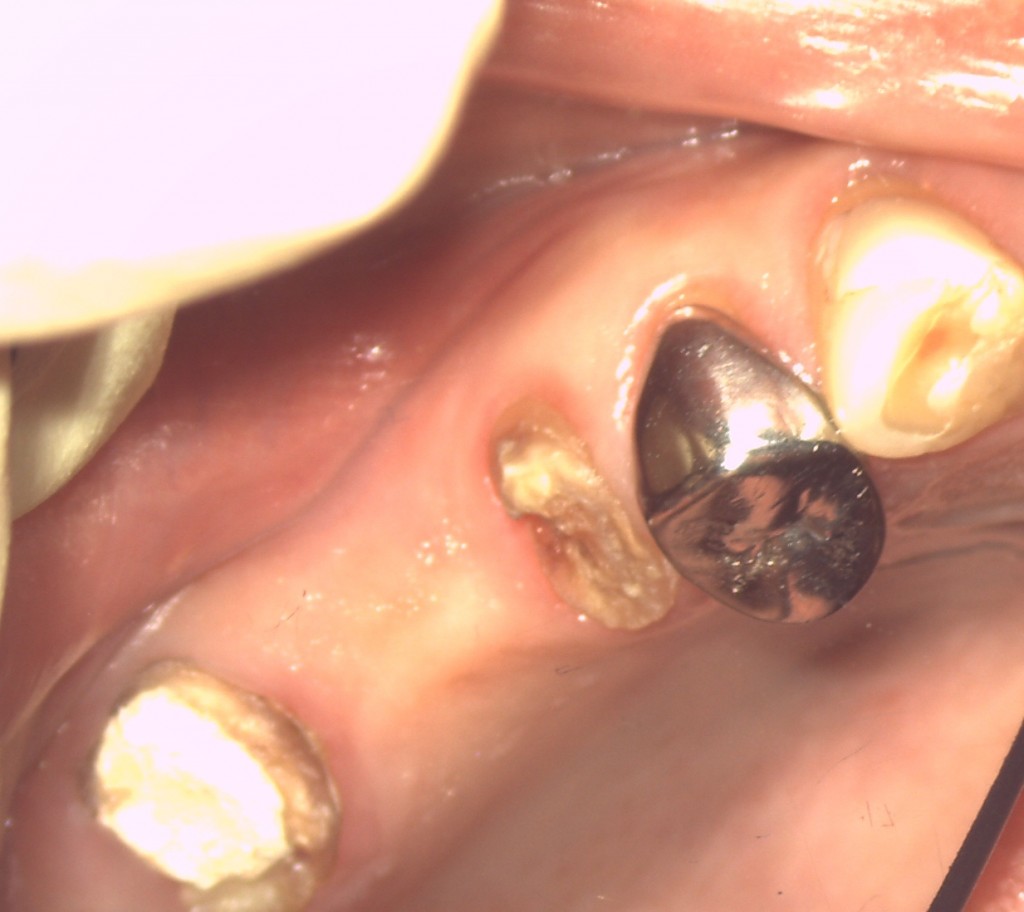

しかし、手前の歯は残根状態でラバーダムが掛かりませんのでダイレクトボンドの手法でラバーダムを掛けて治療をします。

このままの状態で根管治療をしても歯の中に感染が起こり治療は失敗します。

また、薬剤が漏れるとヤケドがおこるので、細心の注意をして隔壁を作ります。保険診療ではこのような方法は点数がないのでやらないということなのでしょうか?